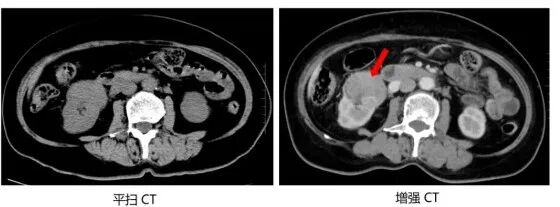

下面我们来看看平扫CT和增强CT的差别。下图分别为肝脏和肾脏平扫CT图像与增强CT图像的比较,在增强CT上医生可更清晰的发现肝脏和肾脏的病变,且对病变的良恶性判断有帮助。